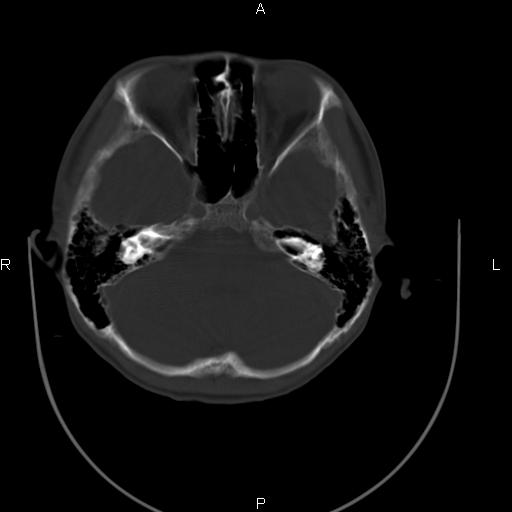

标题: CT27115:大家看一看,这孩子的颅骨表现? [打印本页]

标题: CT27115:大家看一看,这孩子的颅骨表现?

两名中学生打架,脑质内未见异常,未上传。

两例——颅骨结构正常,未见明显骨折征象。